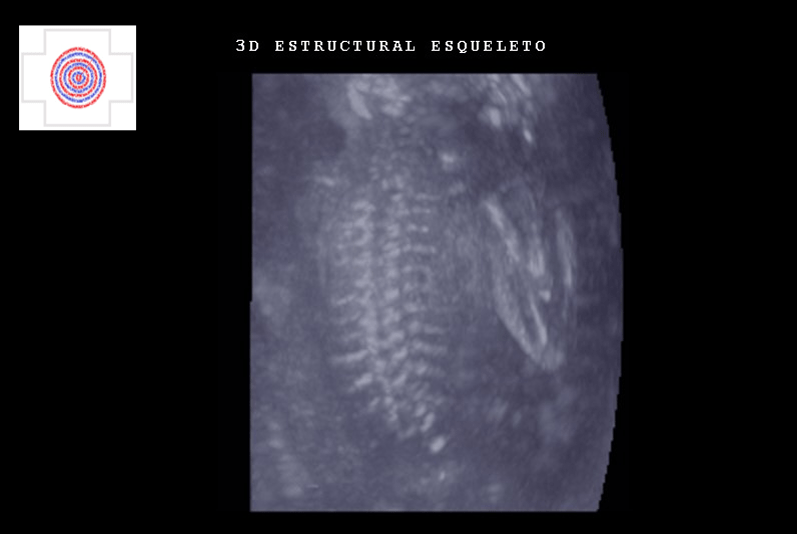

3D ESQUELETO, ESTRUCTURAL, CABEZA, COLUMNA, COSTILLAS.

3D ESTRUCTURAL ESQUELETO, COLUMNA Y COSTILLAS